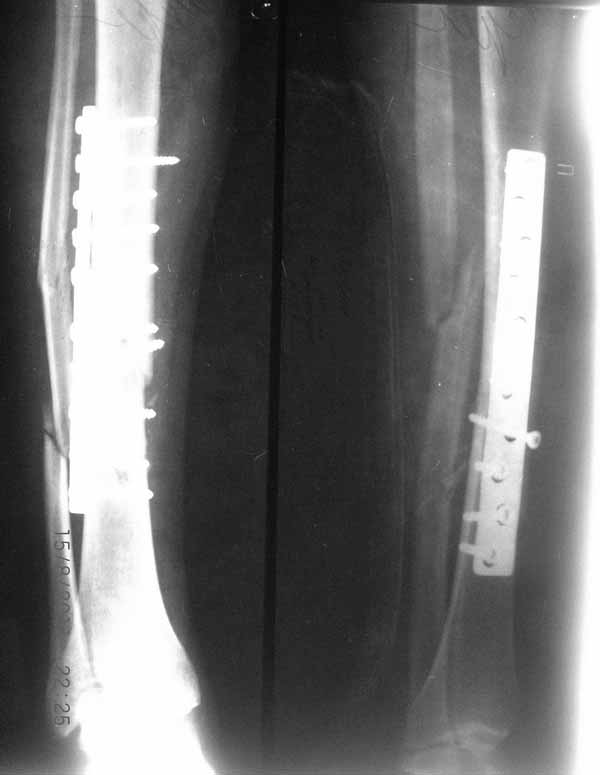

Мне кажется, в первую очередь надо заниматься спицевым остеомиелитом! Надо посмотреть фото голени.

Уважаемый, Иван! Однозначно сказать что концы отломков "мертвые" трудно. Если и делать, то предварительно провести сцинтиографию с технецием и потом решать. Всегда резекцию сделать успеете. Если есть изменения (инфекция) то можно попытаться рассверлить "осиное гнездо" (костную пластику при такой картине я б не советовал-может "вспыхнуть")и исправить аппаратом( восстановить ось)+ штифт с антибактериальным покрытием. В принципе можно оставить и аппарат только за ним очень пристальное внимание. Удачи!

2. после фиксации в аппарате Илизарова на рентгеногнрамме имеются признаки спицевого остеомиелила. В настоящи момент хотя свищей нет с мая 2011 нет опасно ли фиксировать голень стержнем?

На основании каких признаков Вы решили, что кость мертвая! Имеется гиперпластический ложный сустав, как результат недостаточно стабильной фиксации ан предыдущих этапах лечения. В данном случае необходимо решение следующих вопросов:

1 наличие инфекция в зоне ложного сустава

2. коррекция оси

3. окончательная стабильная фиксация

4. исключение предыдущих ошибок

5. оценка своих возможностей.

Открытое вмешательтво на зону ложного сустава, по нашему мнению, не только нецелесообразно, но и вредно! По тактике лечения согласен с Алексеем Семенистым, мы избрали такую- же тактику, но этот вопрос для Вас под номером 5.